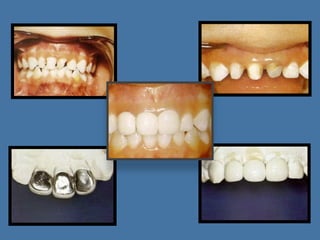

Coroas

de

aço

inoxidável

– Vantagens:

•   Baixo

custo

•   Colocação

requer

pouco

tempo

•   Vários

tamanhos

•   Recuperam

espaço

mesio‐distal

•   Aço

não

mancha

e

resiste

a

todos

os

fluidos

bucais

Coroa

– Desvantagens: